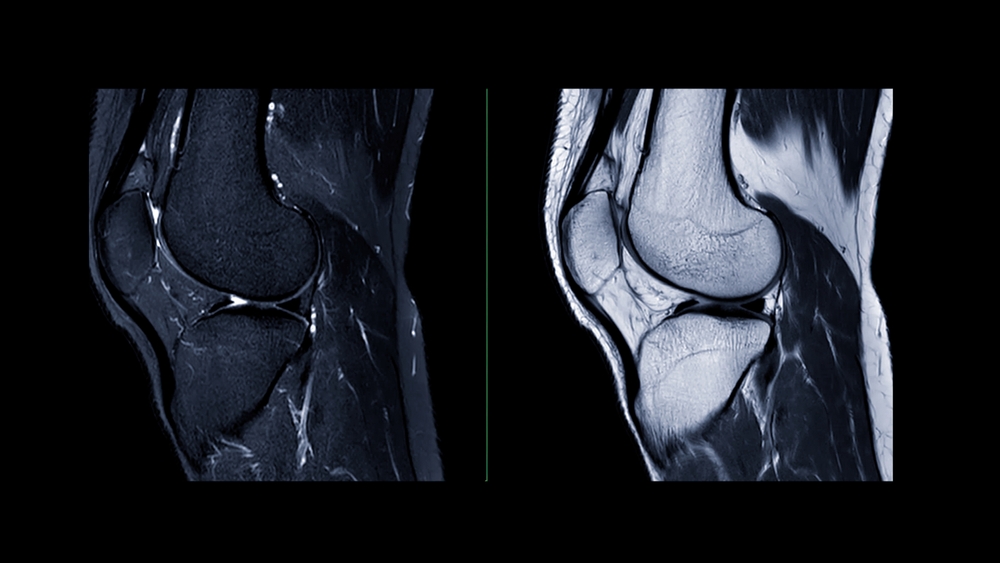

Osteoarthritis is largely a problem of cartilage breakdown.

Osteoarthritis is largely a story about cartilage—the smooth, shock-absorbing tissue that allows bones to glide over each other with minimal friction. Healthy cartilage is extraordinarily slick (often described as even more slippery than ice) and acts like a cushion that protects joints during walking, lifting, and impact.